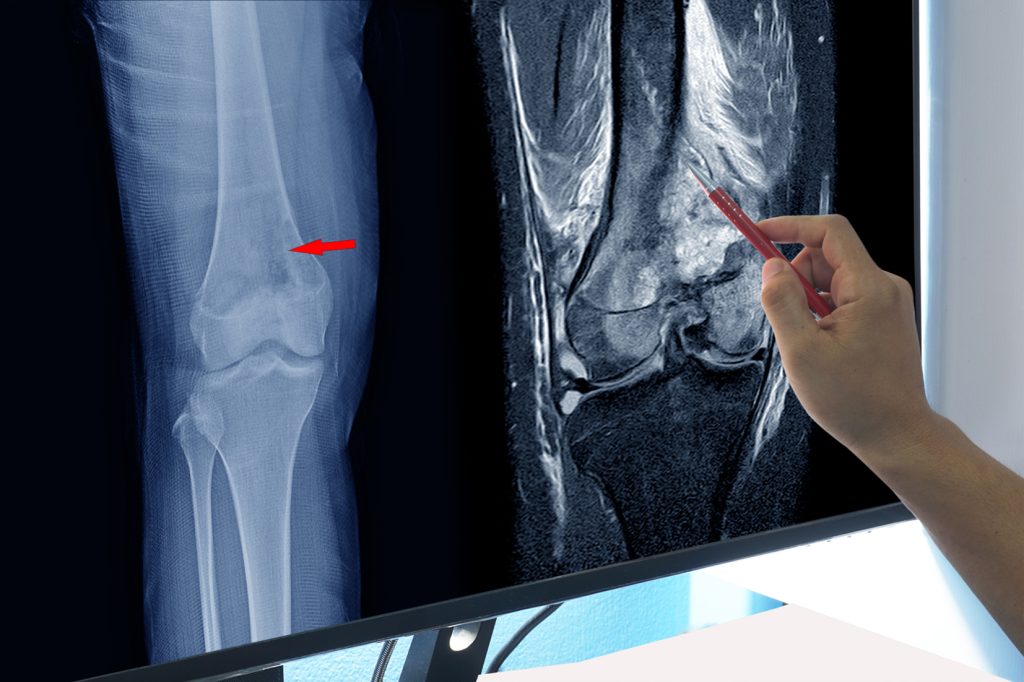

Osteosarkom, koji je najčešći kod djece i adolescenata, obično se javlja u predjelu koljena ili nadlaktice. U početku, bol može biti blag, ali s vremenom postaje intenzivan, što može ometati svakodnevne aktivnosti i kvalitet života. Hondrosarkom, s druge strane, obično pogađa starije osobe i napreduje sporije, ali njegovi simptomi, poput oticanja i bolova, također se mogu ignorisati, što može dovesti do postavljanja dijagnoze u kasnoj fazi.